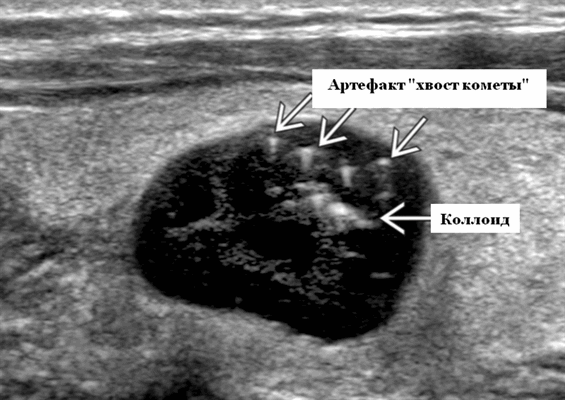

- Характерны эхогенные очаги с артефактами хвоста кометы. Представляют собой суспендированные коллоидные агрегаты

- Лучший диагностический признак - тонкостенные кисты с артефактами хвоста кометы

Ультрасонографические данные. Ультразвуковое сканирование в оттенках серого. Однокамерная тонкостенная киста является типичной находкой. У нее имеется тонкая, эхогенная стенка и анэхогенное содержимое с задним акустическим усилением. Характерны эхогенные очаги с артефактами хвоста кометы, представляющие собой взвешенные коллоидные агрегаты. ± коллоидные скопления (нерегулярный, эхогенный, аваскулярный детрит). Если было предыдущее кровоизлияние в кисту, то она будет толстостенной с детритом ± уровень жидкости. Толстые септы ± кометный хвост, если киста возникает из гиперпластического узла. Фон узла сплошной, а кистозные пространства переменных размеров. Узел будет выглядеть солидным, с хорошо выраженными границами, овальным и, изоэхогенным, а внутри не обнаруживается точечной кальцификации. Коллоидные скопления разбросаны в кистозных пространствах